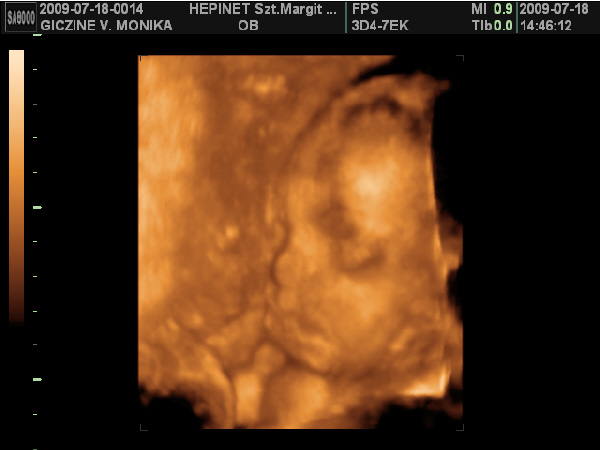

Lányok hoztam nektek képeket: :D :D

Kép

Ezek a képek szombaton készűltek. Bár nehéz volt jó képeket csinálni Lauráról, mert nagyon a méhlepény felé volt fordúlva. :D

Minden tökéletes vele, kb: 1 kilós már.

Ja!

És nagyon hasonlít a bátyjára. :lol: :lol: :lol: